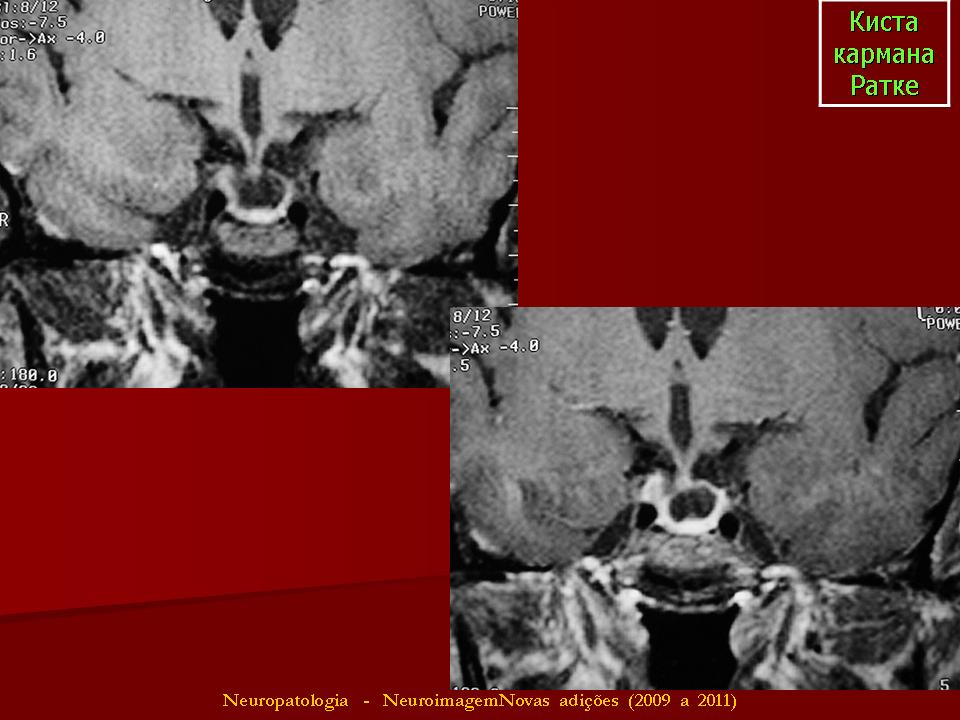

ГМ. Киста кармана Ратке. +

Киста кармана Ратке

Киста кармана Ратке ИМХО должна иметь стенку. На первой серии снимков верхней стенки нет и киста сливается с супраселлярной цистерной, имеет неотличимые от ликвора сигнальные характеристики. Насчёт подстверждения. Вот интересно мне, как можно подтвердить кисту кармана Ратке в данном случае?? Гистологически?

Мне тоже показалось, что в первой серии изображений кистой и не пахнет.Видится "пустое" турецкое  седло с расширенной  супраселлярной цистерной.Оказалось, что не только мне одной.

Именно, формирующеес первичное, в кранем случае вторичное "пустое" турецкое седло. Уважаемый Валентин Львович, прошу прощения за поднятые здесь дебаты, это не неуважение к Вам или вашим источникам, а просто обмен мнениями по поводу спорного на наш взгляд наблюдения. Потом всё можно удалить. Интересно, какие будут мнения у других....